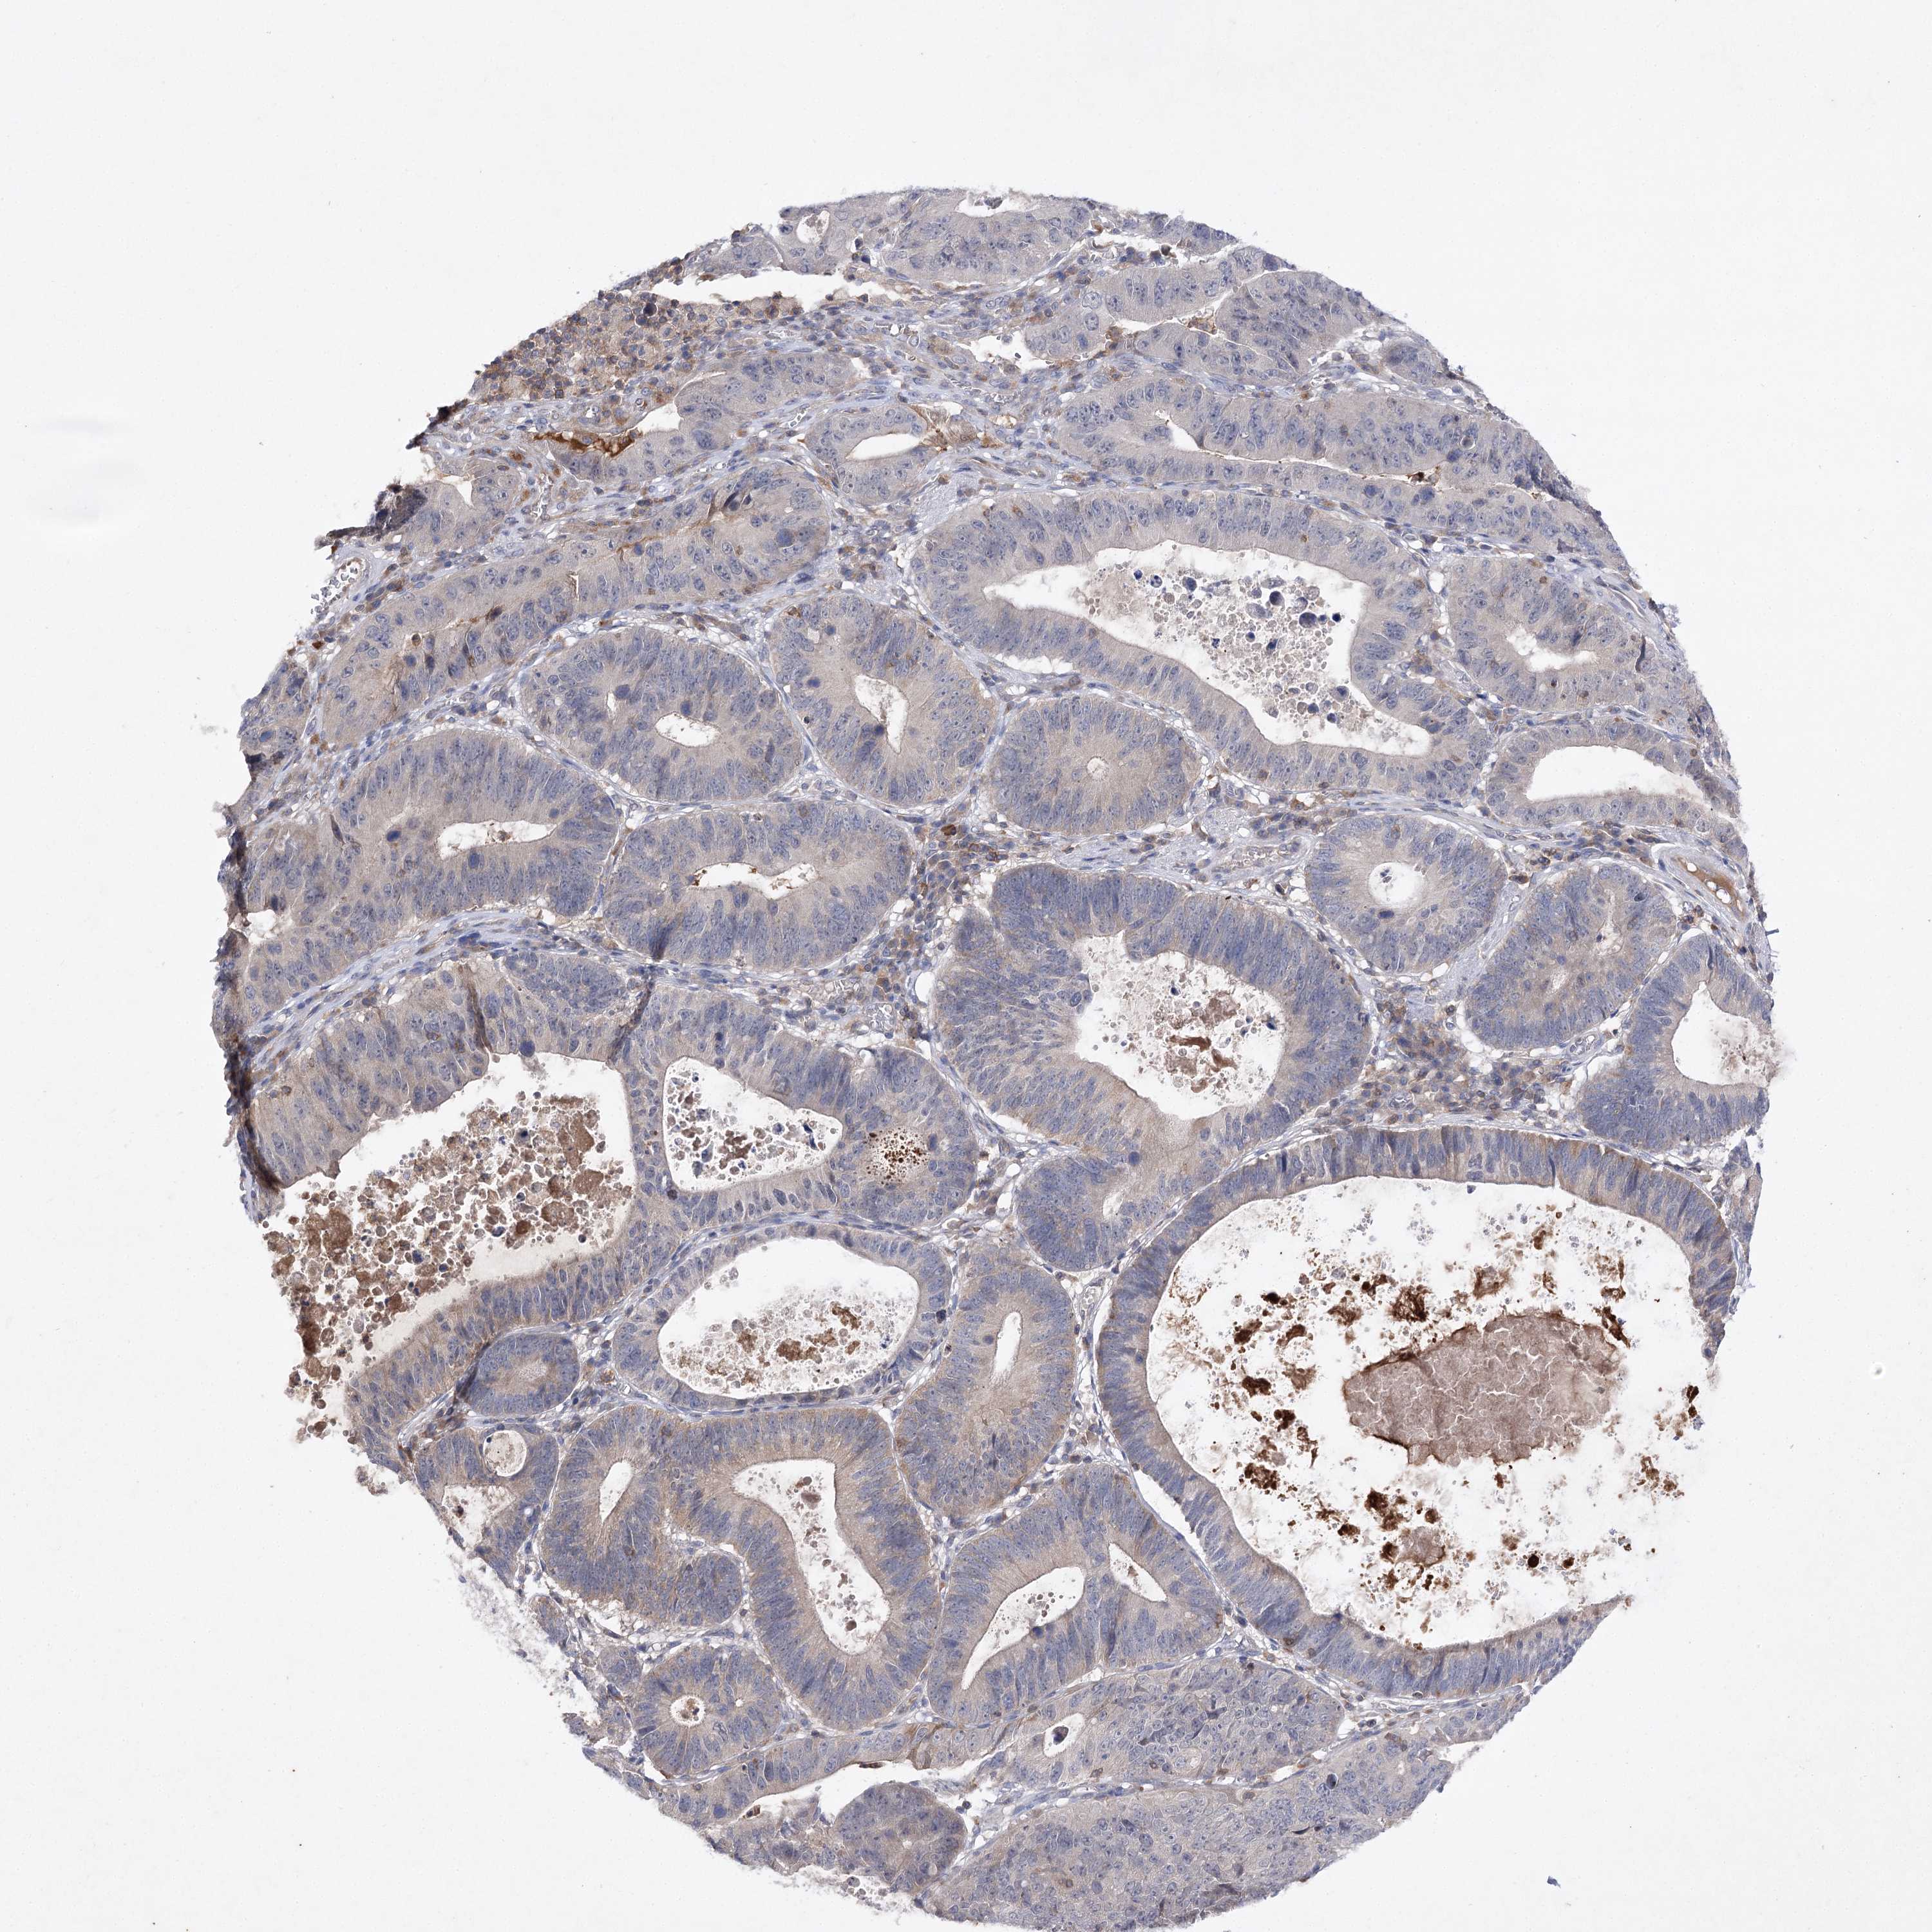

STOMACH CANCER - Protein expressioni

A mouse-over function shows sample information and annotation data. Click on an image to view it in a full screen mode. Samples can be filtered based on level of antibody staining by selecting one or several of the following categories: high, medium, low and not detected. The assay and annotation is described here.

Note that samples used for immunohistochemistry by the Human Protein Atlas do not correspond to samples in the TCGA dataset.

Antibody stainingi

Antibody staining in the annotated cell types in the current human tissue is reported as not detected, low, medium, or high, based on conventional immunohistochemistry profiling in selected tissues. This score is based on the combination of the staining intensity and fraction of stained cells.

Each image is clickable and will lead to virtual microscopy that enables deeper exploration of all samples and also displays staining intensity scores, fraction scores and subcellular localization as well as patient and tissue information for each sample.

Antibody HPA038337

Antibody CAB010421

Antibody CAB018545

Staining

Adenocarcinoma, NOS